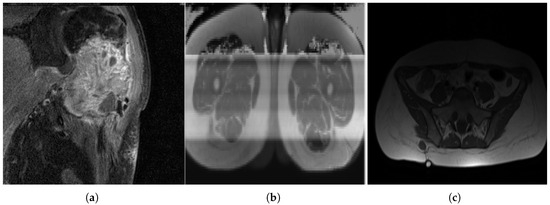

The dataset is complex, as sarcomas are diverse, making generalization difficult [8]. Variations in MRI scan protocols, such as differing contrast, fat suppression and weighting methods, contribute to variability in tumor appearance (Figure 3). Considering multiple orientations—axial, coronal and sagittal—adds complexity that the model must handle. Additionally, differences in gray-value ranges and MRI specifications complicate standardization. Some sarcoma types, like OS, are under-represented, making grade classification challenging, as the model may misclassify OS as a lower grade. Including sarcoma subtype information could improve classification.

Non-pathological tissue was grouped as healthy, which can cause misclassification, as biological tissue may resemble pathological regions (Figure 4). Small homogeneous regions in segmented 3D images may confuse the model, especially when similar to healthy tissue. Image quality varied significantly between patients (Figure 5), with some images being grainy, blurred or corrupted, which may affect model performance.

Figure 3. MRI slices: (a) A case of OS where the machine uses specific settings and contrast media to brighten the tumor region and suppress fat response. (b) Another patient (with liposarcoma in this case) where the tumor region is dark in contrast and fat tissue is not suppressed.

Figure 5. Variance in image quality. (a) A grainy slice with relatively high noise. (b) A corrupted image. (c) An example of uneven lighting distribution.